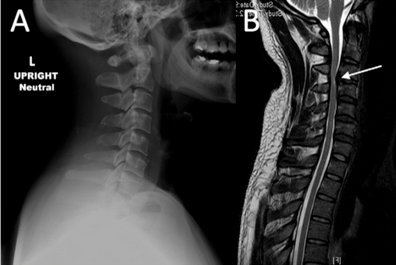

颈椎骨折导致椎动脉损伤!